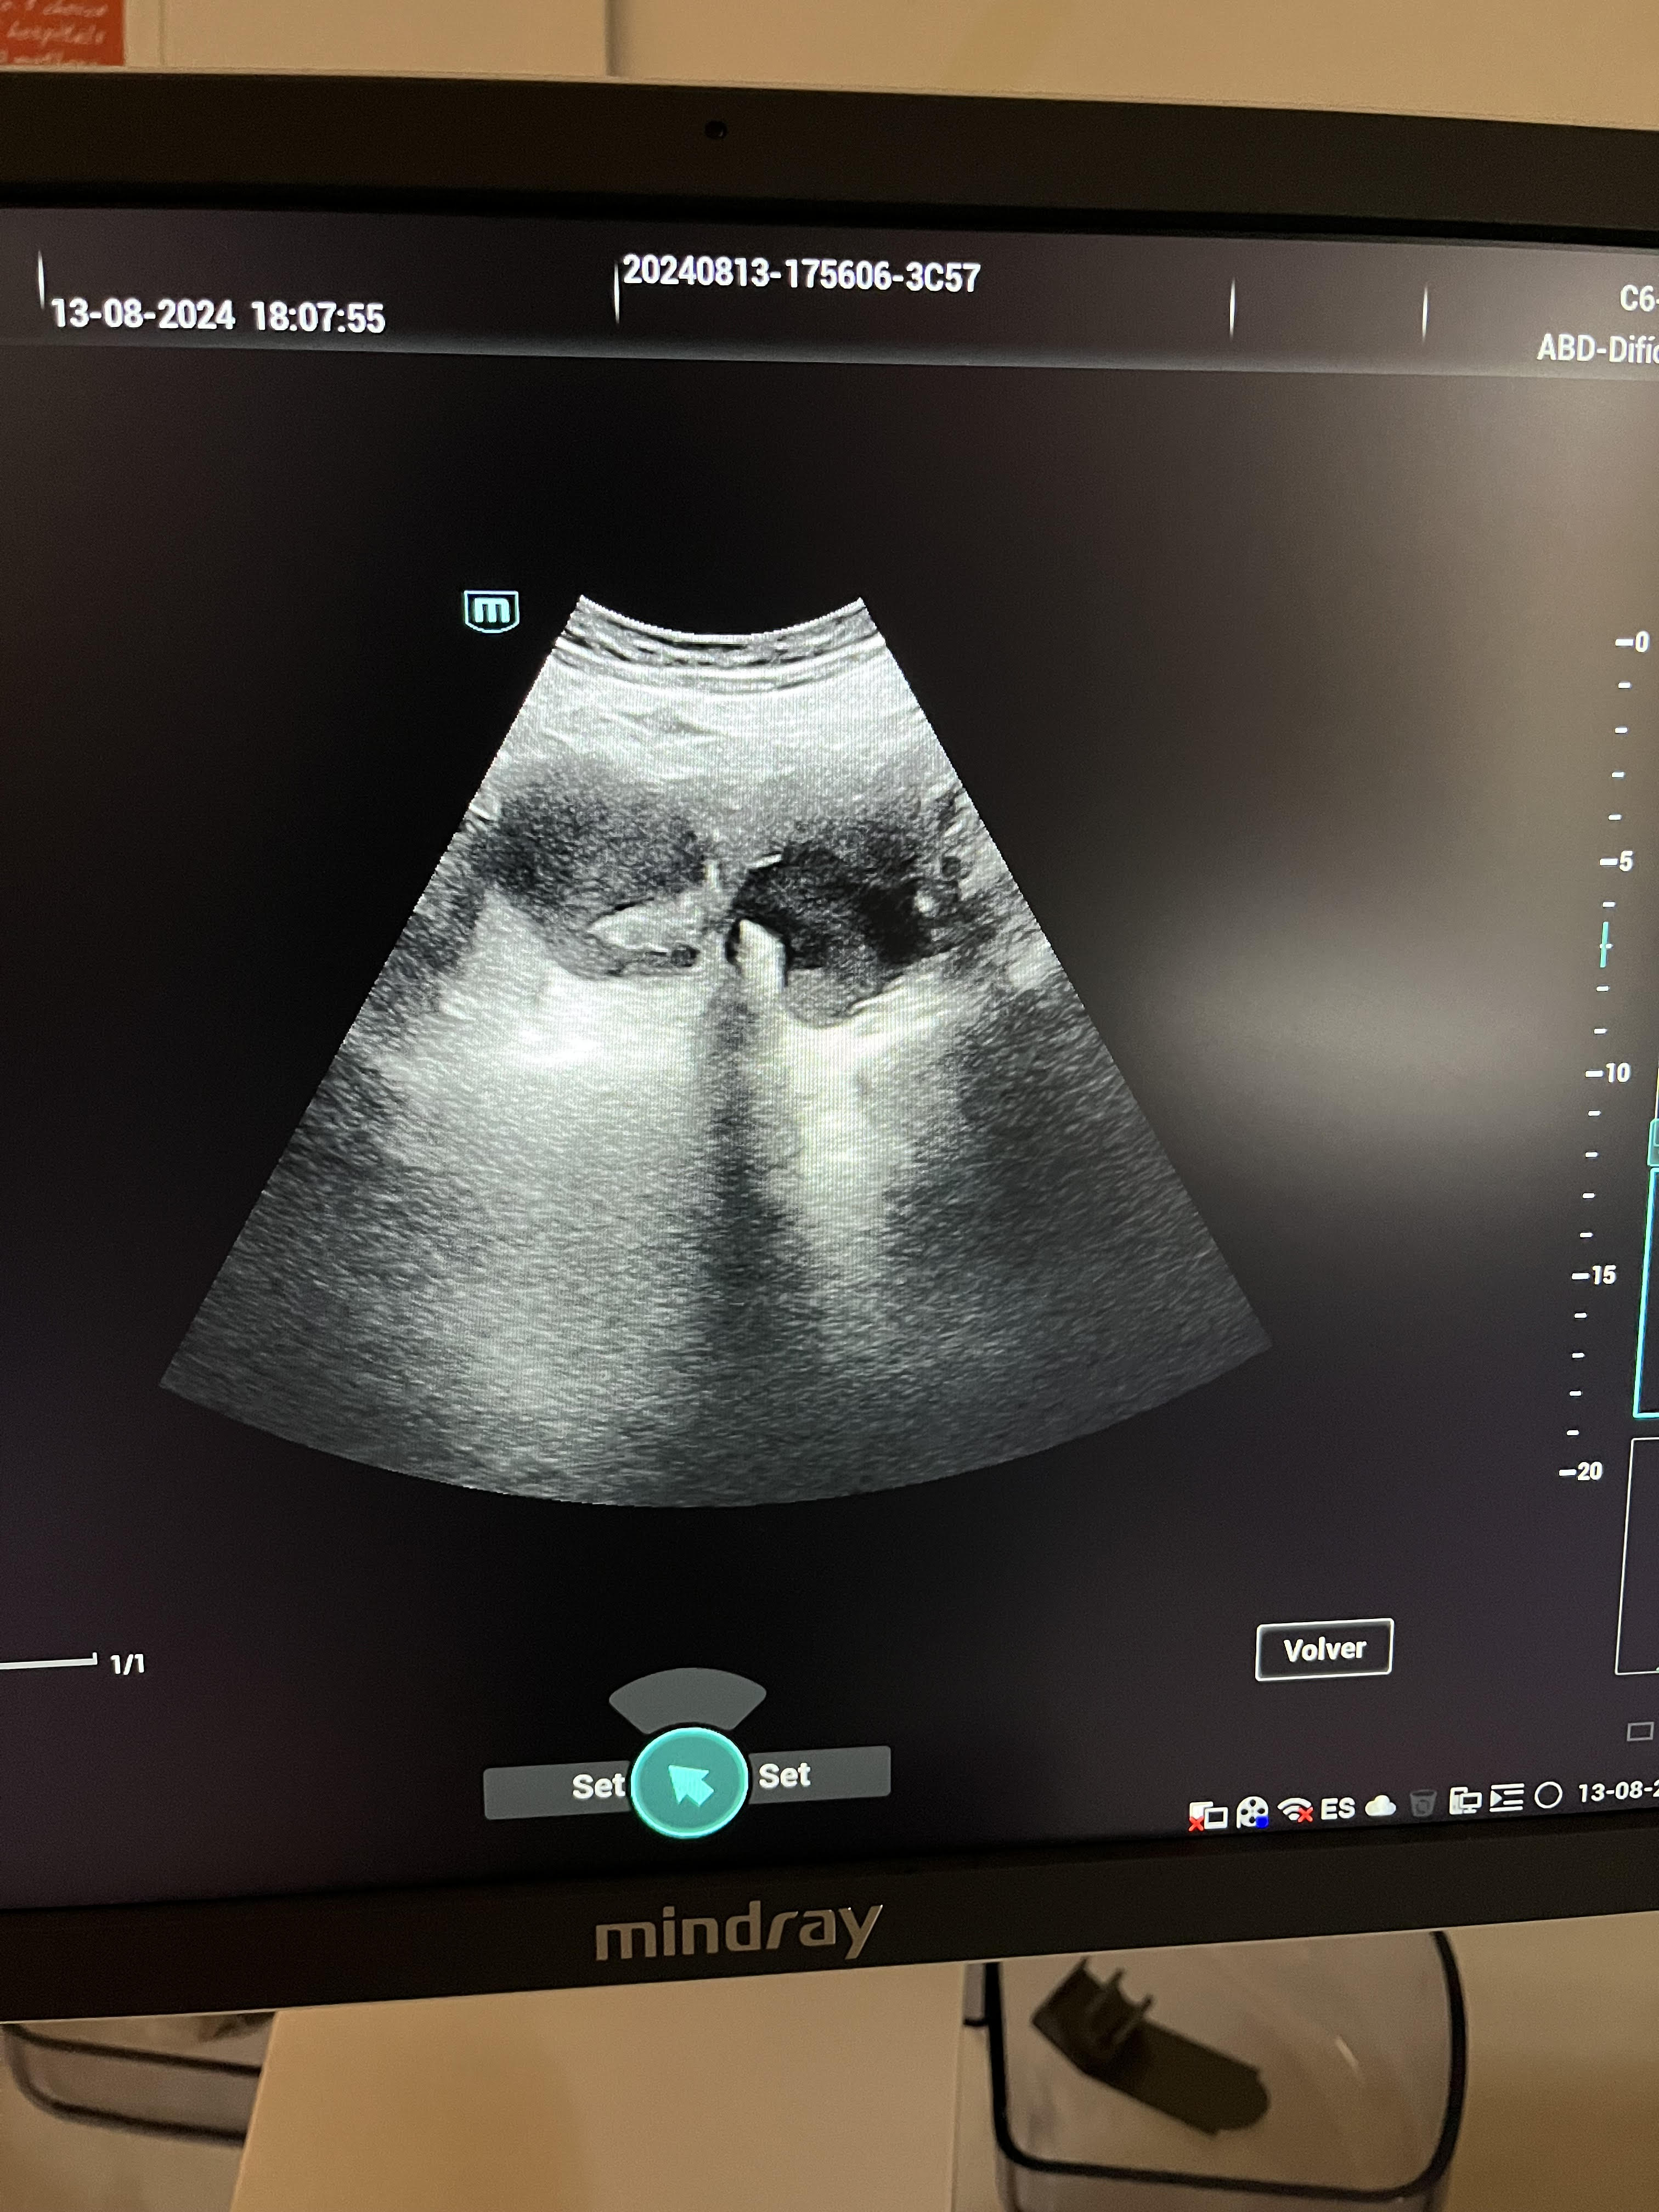

La ecografía revela un útero desplazado por una tumoración quística de contenido hipoecoico de 77 x 63 mm en el lado derecho, sin captación de señal Doppler. La anatomía uterina no se visualiza claramente, y se observa una línea endometrial irregular.

La sospecha principal fue de endometrioma, considerándose el diagnóstico diferencial con mioma uterino. En la valoración hospitalaria, se confirma el hallazgo de endometriosis.

En la valoración hospitalaria mediante ecografía ginecológica reglada, se describe un útero de 90 x 55 x 58 mm con signos de adenomiosis: asimetría miometrial (miometrio anterior de 16 mm y posterior de 33 mm), quistes de la unión miometrial y miometrio dishomogéneo. Cavidad en signo de interrogación (question mark sign), junto con quistes endometriósicos de gran tamaño a nivel axial bilateral, lo que sugiere endometriosis profunda. Se pauta tratamiento con progestágeno, a la espera de evaluar la evolución y considerar la posibilidad de una histerectomía radical con salpingooforectomía bilateral.